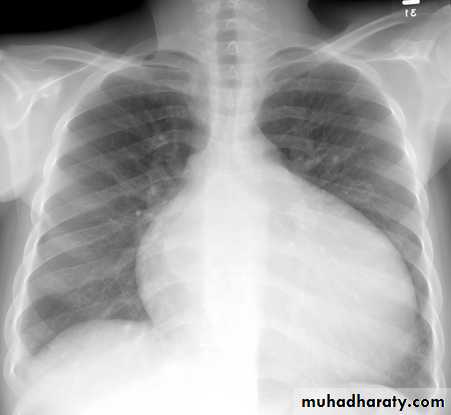

Chest X-Ray: cardiomegaly and pulmonary congestion

CXR